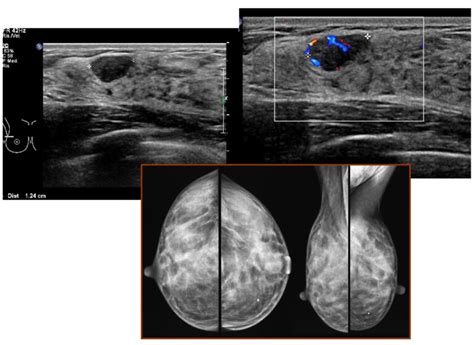

L’ecografia mammaria è un esame diagnostico non invasivo che utilizza ultrasuoni per studiare la struttura del seno in dettaglio. Per la sua esecuzione, viene impiegata una sonda lineare specifica, la quale ha la capacità di emettere ultrasuoni ad alta frequenza sulla zona da esplorare. Questi ultrasuoni, una volta che incontrano i tessuti mammari, vengono riflessi in modo differente a seconda della densità e della struttura delle varie componenti che attraversano. Tali segnali riflessi sono poi interpretati da un apposito software, integrato nell'apparecchio ecografico, che ha il compito di generare un’immagine visibile sullo schermo, fornendo al medico una rappresentazione dettagliata delle strutture interne del seno.

È fondamentale comprendere che l’ecografia mammaria non è un’alternativa alla mammografia, bensì i due accertamenti rappresentano l’uno il completamento dell’altro. Questi esami, infatti, non sono alternativi, ma complementari. L'ecografia mammaria non è un'alternativa alla mammografia e i due esami sono pertanto da considerarsi complementari, poiché analizzano il seno fornendo informazioni diverse che possono essere integrate per una diagnosi più accurata. Entrambe le metodiche sono indispensabili per una valutazione completa e approfondita della salute del seno, ognuna con le sue specificità e indicazioni.

La distinzione principale tra le due metodiche risiede nella tecnologia utilizzata: per la mammografia, infatti, si fa ricorso all’impiego di raggi X, una forma di radiazioni ionizzanti, mentre l’esame ecografico impiega innocui ultrasuoni. Questa differenza tecnologica comporta importanti implicazioni pratiche e cliniche. Ne consegue che le ecografie mammarie, a differenza della mammografia, possono essere ripetute a più riprese, anche ad intervalli di tempo ravvicinati tra loro, senza alcuna preoccupazione per la salute della paziente. L'ecografia non è nociva e assicura un alto livello di precisione nella diagnosi di svariate patologie, soprattutto nelle pazienti in età giovane, dove, come già menzionato, la densità ghiandolare può rendere la mammografia meno sensibile.

Un altro aspetto cruciale in cui l'ecografia mammaria si rivela insostituibile è il suo utilizzo come guida in procedure interventistiche. In caso di biopsia, ad esempio, l’ecografia mammaria viene impiegata per guidare con estrema precisione l’ago nel punto esatto in cui effettuare il prelievo di tessuto, garantendo l'accuratezza del campionamento e minimizzando il disagio per la paziente. L’ecografia mammaria è uno dei mezzi diagnostici più efficaci nell’indagine delle ghiandole mammarie e dei linfonodi ascellari, fornendo una visione dettagliata che permette di identificare anche le più piccole anomalie.